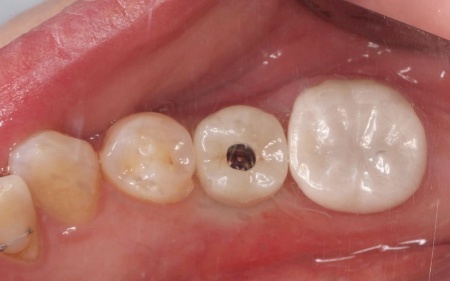

拝見したところ、左上奥歯(第1小臼歯)は歯の上の部分である歯冠が折れ、歯根のみ残っている状態でした。

また、左下奥歯(第2小臼歯)には被せ物が装着されています。

診断結果をお伝えし、患者様の了承を得たうえで左下奥歯の被せ物を外したところ、レントゲン検査での診断どおり、歯根が割れていることが確認できました。